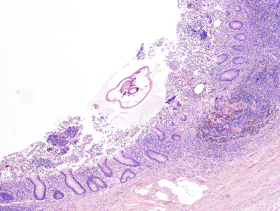

Answer: As stated very nicely by MicrobeMan, "This is...a case of enterobiasis (

Enterobius vermicularis). Some diagnostic features which are nicely demonstrated in the appendix cross-sections include alae, intestines, ovaries, and the hard-to-mistake eggs (which I think look like little loaves of bread). Perhaps treatment with a benzimidazole drug or pyrantel pamoate is indicated in this case. Also, prophylactic treatment of close contacts might be warranted, since this poor fellow is a probably a nidus of infection for countless others with whom he physically interacts on a daily basis."

Note that there is a granuloma and several pinworms within the actual wall of the appendix:

Pinworms can be identified in cross-section by their characteristic lateral alae (arrows, below), and the presence of the eggs in gravid females.